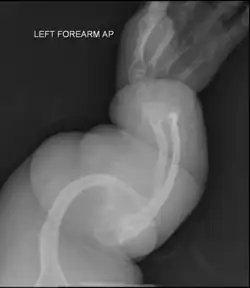

Left forearm

Four X-rays of a 24-year-old American man (Fredrick Brennan), who had had more than one hundred bone fractures in his lifetime, and received a childhood clinical diagnosis of type IV–B OI. Genetic diagnosis in 2018 identified a previously uncatalogued pathogenic variant in the gene which encodes proα2(I) chains of type I procollagen, COL1A2, at exon 19, substitution c.974G>A. Due to childhood neglect and poverty, Brennan never received surgery to implant intramedullary rods. Malunions are evident as the humerus and femur were broken in adolescence, but orthopedic care did not follow. Severe scoliosis, as well as kyphosis, are also evident. The unavoidably low contrast in the film is due to a combination of Brennan's obesity and low bone mineral density (BMD). His BMD Z-score was -4.1 according to results of a dual-energy X-ray absorptiometry (DXA) scan also done in 2018.